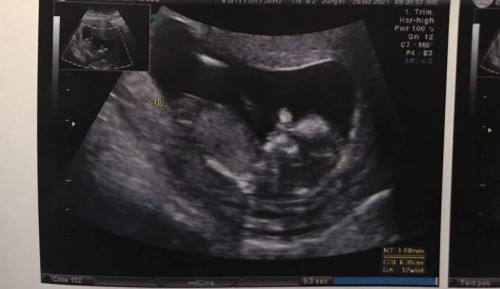

ตั้งครรภ์13w คุณหมอแจ้งผู้หญิง80%

มีใครคุณหมอบอกผู้หญิงแล้วได้ลูกชายบ้างคะ ? ถ้าให้ชัวร์ต้องประมาณกี่สัปดาห์คะ #ขอบคุณสำหรับคำตอบค่ะ

20 สัปดาห์ค่ะ

19-20ค่ะ